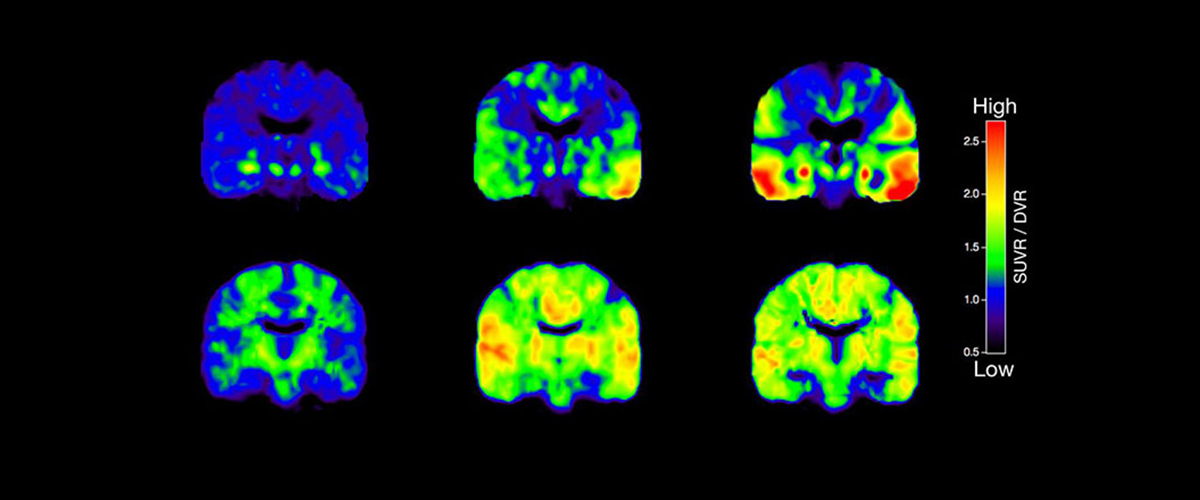

Perfüzyon MR ( Perfüzyon Görüntüleme), vücut dokularına giden kan akışını (perfüzyonu) değerlendirmek için kullanılan ileri bir manyetik rezonans görüntüleme (MR) yöntemidir. Bu teknik, özellikle beyin ve tümörlerin incelenmesi başta olmak üzere birçok klinik alanda kullanılmaktadır.

• Nörodejeneratif Hastalıklar: Alzheimer gibi hastalıklarda beyin kan akımındaki değişiklikleri değerlendirir.

• CBF (Cerebral Blood Flow): Dokuya belirli bir zaman diliminde giden kan akışı miktarı.

• CBV (Cerebral Blood Volume): Doku içindeki toplam kan hacmi.

• MTT (Mean Transit Time): Kanın dokudan geçiş süresi.

• TTP (Time to Peak): Kontrast maddenin dokuda maksimum yoğunluğa ulaşma süresi.